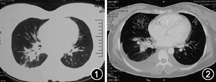

患者女,32岁。已婚,汉族,护士。因发热伴胸闷、气急1周于2013年1月10日以"肺炎"收入院。患者于2012年12月8日顺产一女。产后第10天出现一次发热,体温39℃,静脉滴注美洛西林钠(4 g,2次/d)3 d后热退。入院一周前再次出现畏寒发热,体温最高40℃,伴有咽痛,咳嗽、咳少许白痰,胸闷气急,再次静脉滴注美洛西林钠(4 g,2次/d)治疗2 d未见缓解。后至当地医院住院,胸部CT:右下肺炎症,右侧胸腔积液(图1)。静脉滴注哌拉西林/他唑巴坦(4.5 g,1次/8 h)、莫西沙星(0.4 g,1次/d)治疗3 d,体温无明显下降,2013年1月8日起静脉推注甲泼尼龙(40 mg,2次/d),静脉滴注丁胺卡那(0.4 g,1次/d),口服乙胺丁醇片(0.75 g,1次/d),治疗2 d后体温波动在37.5~38.0℃。病程中患者胸闷气急进行性加重。既往体健,2年前流产一次。否认慢性病及传染病史。无吸烟、饮酒嗜好。

实验室检查:WBC 1.21×109/L,RBC 3.2×1012/L,中性粒细胞百分比0.735,Hb 72 g/L,PLT 40×109/L;ESR 10 mm/1 h,C反应蛋白30 g/L;ALT 146 U/L,AST 210 U/L,乳酸脱氢酶(LDH) 613 U/L;肾功能、电解质正常;血清降钙素原2.05 μg/ml;血T淋巴细胞亚群:CD4T淋巴细胞/CD8T淋巴细胞比值1.9;2次查(1,3)–β–D–葡聚糖均<10 pg/ml;结核感染T细胞检测为无反应性;D–二聚体10 mg/L。抗核抗体、核周型抗中性粒细胞胞浆抗体、胞浆型抗中性粒细胞胞浆抗体、抗平滑肌抗体、抗线粒体抗体、抗核糖体抗体均为阴性,抗单链DNA抗体5 RU/ml,抗双链DNA抗体<10 IU/ml,抗心磷脂抗体<12 RU/ml,抗肾小球基底膜抗体<20 RU/ml,类风湿因子<20 IU/ml,抗溶血性链球菌素60.4 IU/ml,均在正常范围内。1月11日胸部CT:右下肺炎症较入院前无明显变化,但胸腔积液增多(图2)。1月11日骨髓穿刺及活检:骨髓增生轻度低下骨髓象,各阶段红系和粒系形态基本正常,结合免疫组化提示轻度增生骨髓象。